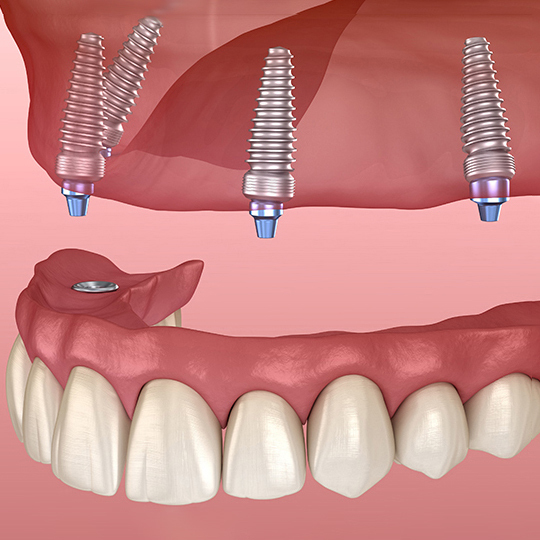

「オールオンX」とは、少ない本数のインプラントで、多数の人工の歯を固定する治療法の総称です。

「オールオン4」や「オールオン6」が代表的であり、オールオン4は、片あごにつきわずか4本のインプラントで12本前後の人工の歯を支えます。これは世界的に確立された治療法です。

オールオンX

(オールオン4、6、8)

あごの骨に4~6本のインプラントを埋め込み、それらを基盤として上部構造(被せ物)を固定する治療法です。上下どちらかの全ての歯を失ってしまった場合、従来のインプラント治療では10本以上のインプラントをあごの骨に埋め込む必要がありました。一方オールオンXなら、4~6本のインプラントを埋め込むだけで噛む機能の改善が期待できます。